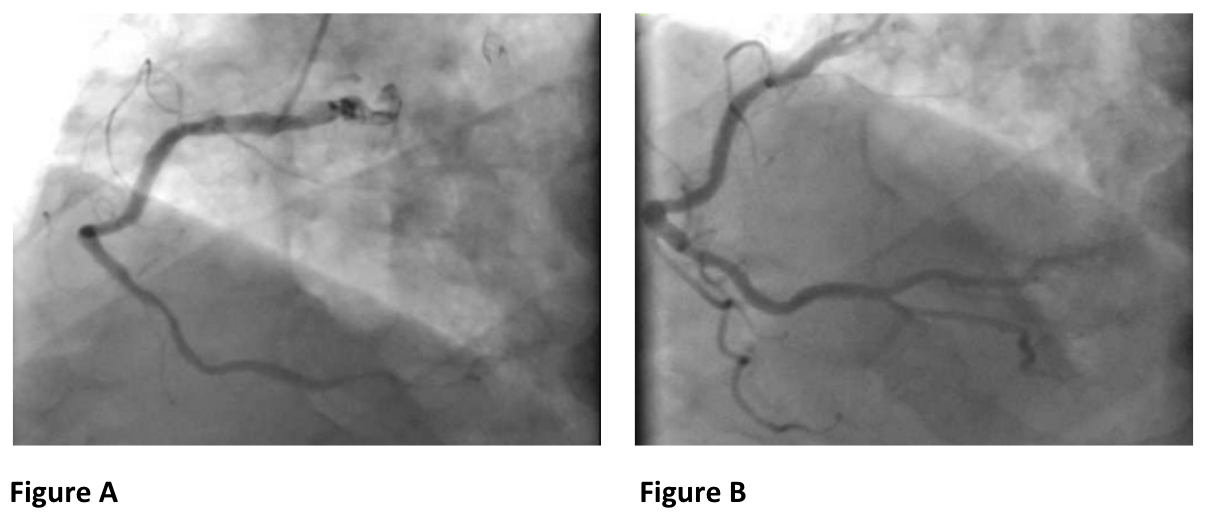

Abstract Body (Do not enter title and authors here): CASE DESCRIPTION: A 74-year-old male with hypertension, hyperlipidemia, coronary artery disease status post PCI, paroxysmal atrial fibrillation, and coronary vasospasm presented with recurrent episodes of chest pain at rest described as substernal, pressure like, 10/10 lasting for a few minutes. The patient was hemodynamically stable upon presentation but had an event of pulseless ventricular tachycardia (VT) requiring shock x 2 (Image 1). The patient was stabilized, and an emergent left heart catheterization showed stable obstructive CAD with diffuse coronary vasospasm responsive to intracoronary nitrates (Image 2). The patient was transferred to the intensive care unit for further management. He had multiple prior presentations for chest pain, with one complicated by a transient hemodynamically unstable high grade AV block (Image 1). Prior work up was also consistent with coronary vasospasm despite being optimally managed on nitrates and calcium channel blockers. Despite medical management the patient had a refractory course with recurrent symptoms. CLINICAL DECISION MAKING: As it was believed that symptoms were likely driven by high sympathetic tone, the patient was intubated and sedated for sympathetic drive suppression. After a multidisciplinary meeting with cardiothoracic surgery and electrophysiology, a decision was made to go for video assisted thoracoscopic surgery (VATS) which was performed successfully. The patient was extubated, had no recurrence of symptoms after, and was offered an implantable-cardioverter defibrillator at discharge for secondary prevention. DISCUSSION: Coronary vasospasm can be life threatening due to transient and acute ischemia driven myocardial injury or arrhythmias. This case highlights the role of VATS sympathectomy in managing severe cases of vasospastic angina that are unresponsive to conventional treatments. Further studies are required to establish the efficacy and safety of this procedure in broader patient populations.